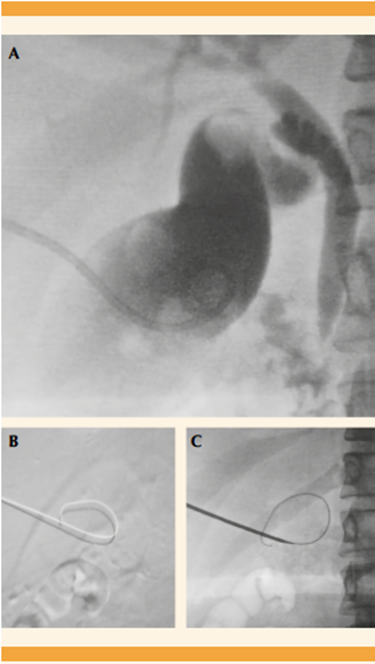

Al décimosexto día hospitalización se practicó una colecistostomía percutánea, guiada por ecografía, con acceso subcostal (Figura 4) y se obtuvieron 20 mL de material biliar espeso. La adecuada situación del sistema de micropunción se corroboró con la aplicación de medio de contraste y fluoroscopia (Figura 5). Posteriormente se llevó a cabo el intercambio mediante un sistema derivativo, con extremo distal alojado en el interior de la vesícula biliar y se fijó a la piel. El extremo proximal se conectó al sistema por gravedad.

Figura 5 (A) Imagen por fluoroscopio en la que se observan la vesícula y el árbol biliar. (B) y (C) Control fluoroscópico poscolecistostomía.